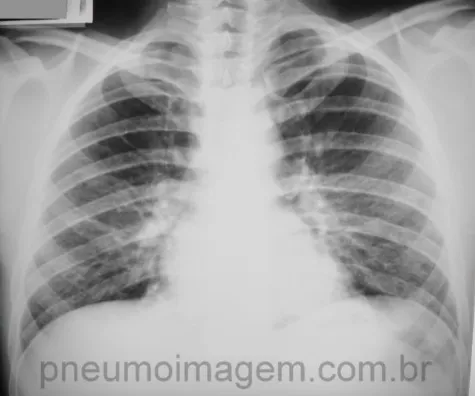

<b>HIV</b> + tosse seca, dispneia aos esforços, quadro arrastado, ausculta normal, com perda de peso.<br><img src="5d4be177c5bbb5275b3b56102b079f89.webp"><br>Suspeita: {{c1::pneumocistose (PCP)}}<br>Exame obrigatório: {{c1::gasometria}} com {{c1::hipoxemia e alcalose resp}}<br>Laboratorial: {{c1::LDH}}>500

RX: infiltrado bilateral (dos hilos para as bases). Pode ter pneumatoceles* (cavidade cística). Pode ser normal.

NÃO tem adenopatia hilar e derrame pleural

*Podem evoluir para pneumotórax (DD com TB e pnm bac).